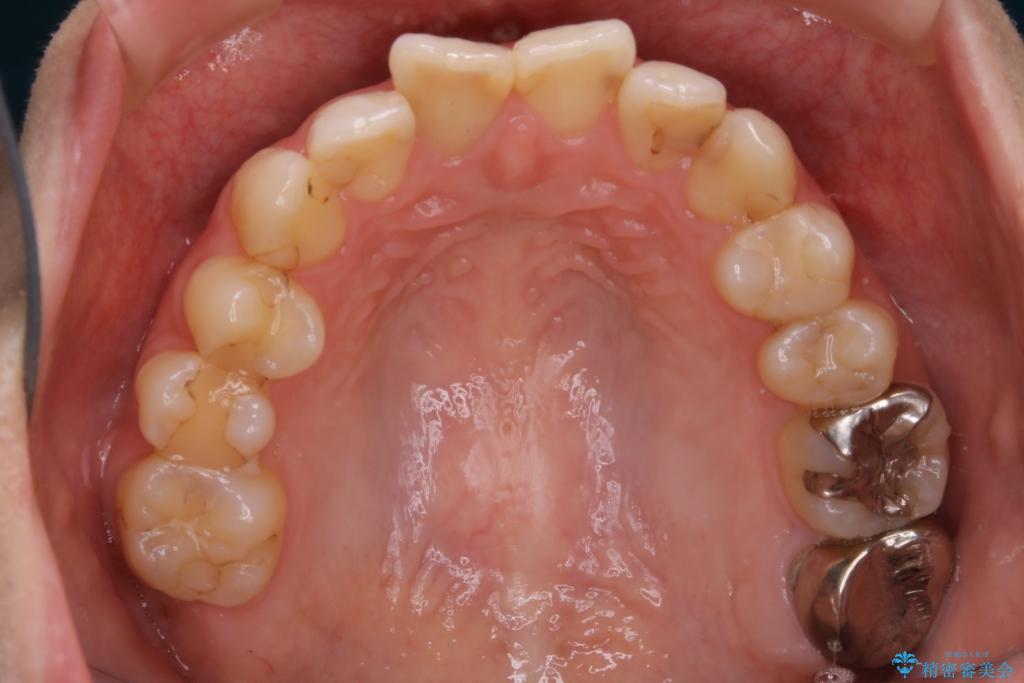

- 前歯のガタつきと噛み合わせの改善を希望してご来院されました。

目立たない装置での矯正治療をとのことでインビザラインを用いた非抜歯矯正を行うこととなりました。

虫歯の治療などが必要な部位がある場合には矯正治療に先立ち全体の状態をよくする術前治療が行われます。